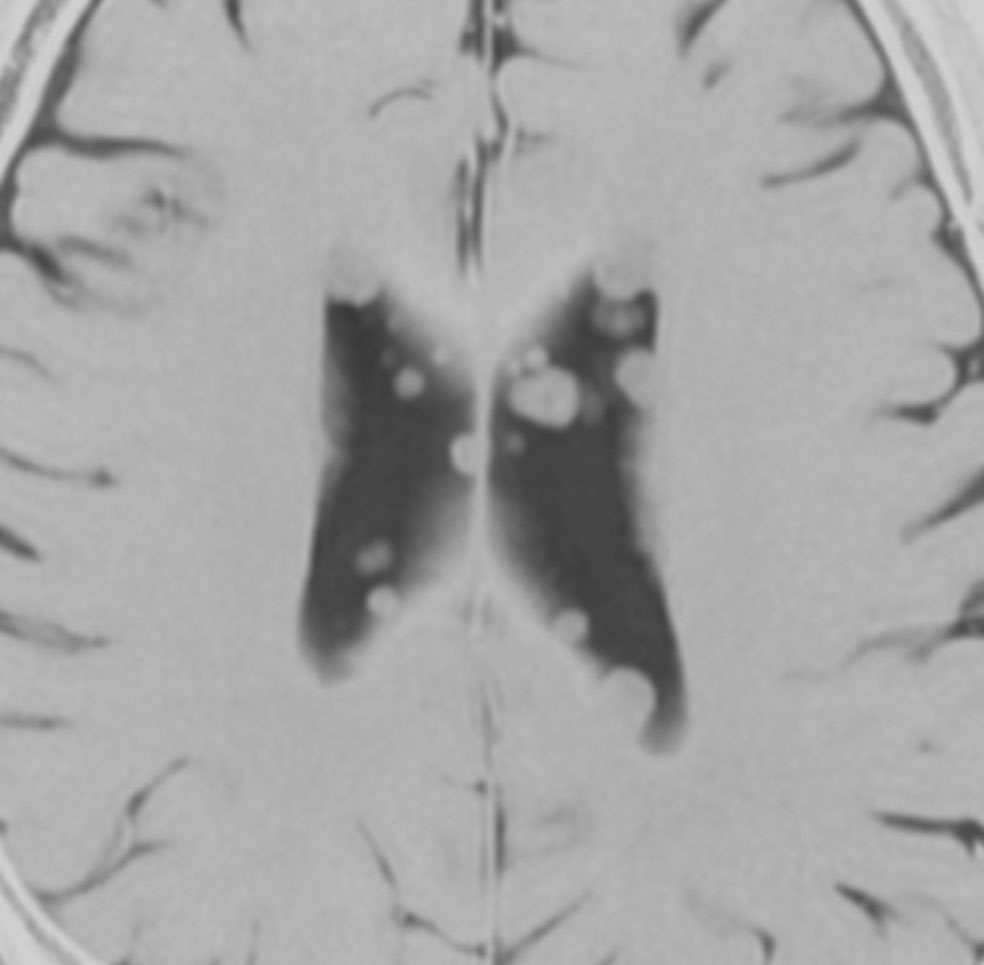

乳児期にてんかん発作で発症した結節性硬化症

黄色の矢印で示すように脳室の壁に多数の小結節 (subependymal nodule SEN) があります。これらの結節はCTでは石灰化としてはっきり描出されますからCTの方が見やすいといえます。赤の矢印で示したのは,左前角 (caudothalamic groove) の腫瘍はSEGAですが,8年間観察してもほとんど増大しませんでした。でも今後に大きくなる可能性は否定できないものですから,これから何年も経過観察が必要です。

黄色の矢印は右の三角部のSEGAです。右の写真で大脳の皮質下白質が白くにじんで見える大脳皮質結節(cortical tubers) のも結節性硬化症の特徴です。このような病変がてんかん発作を生じます。